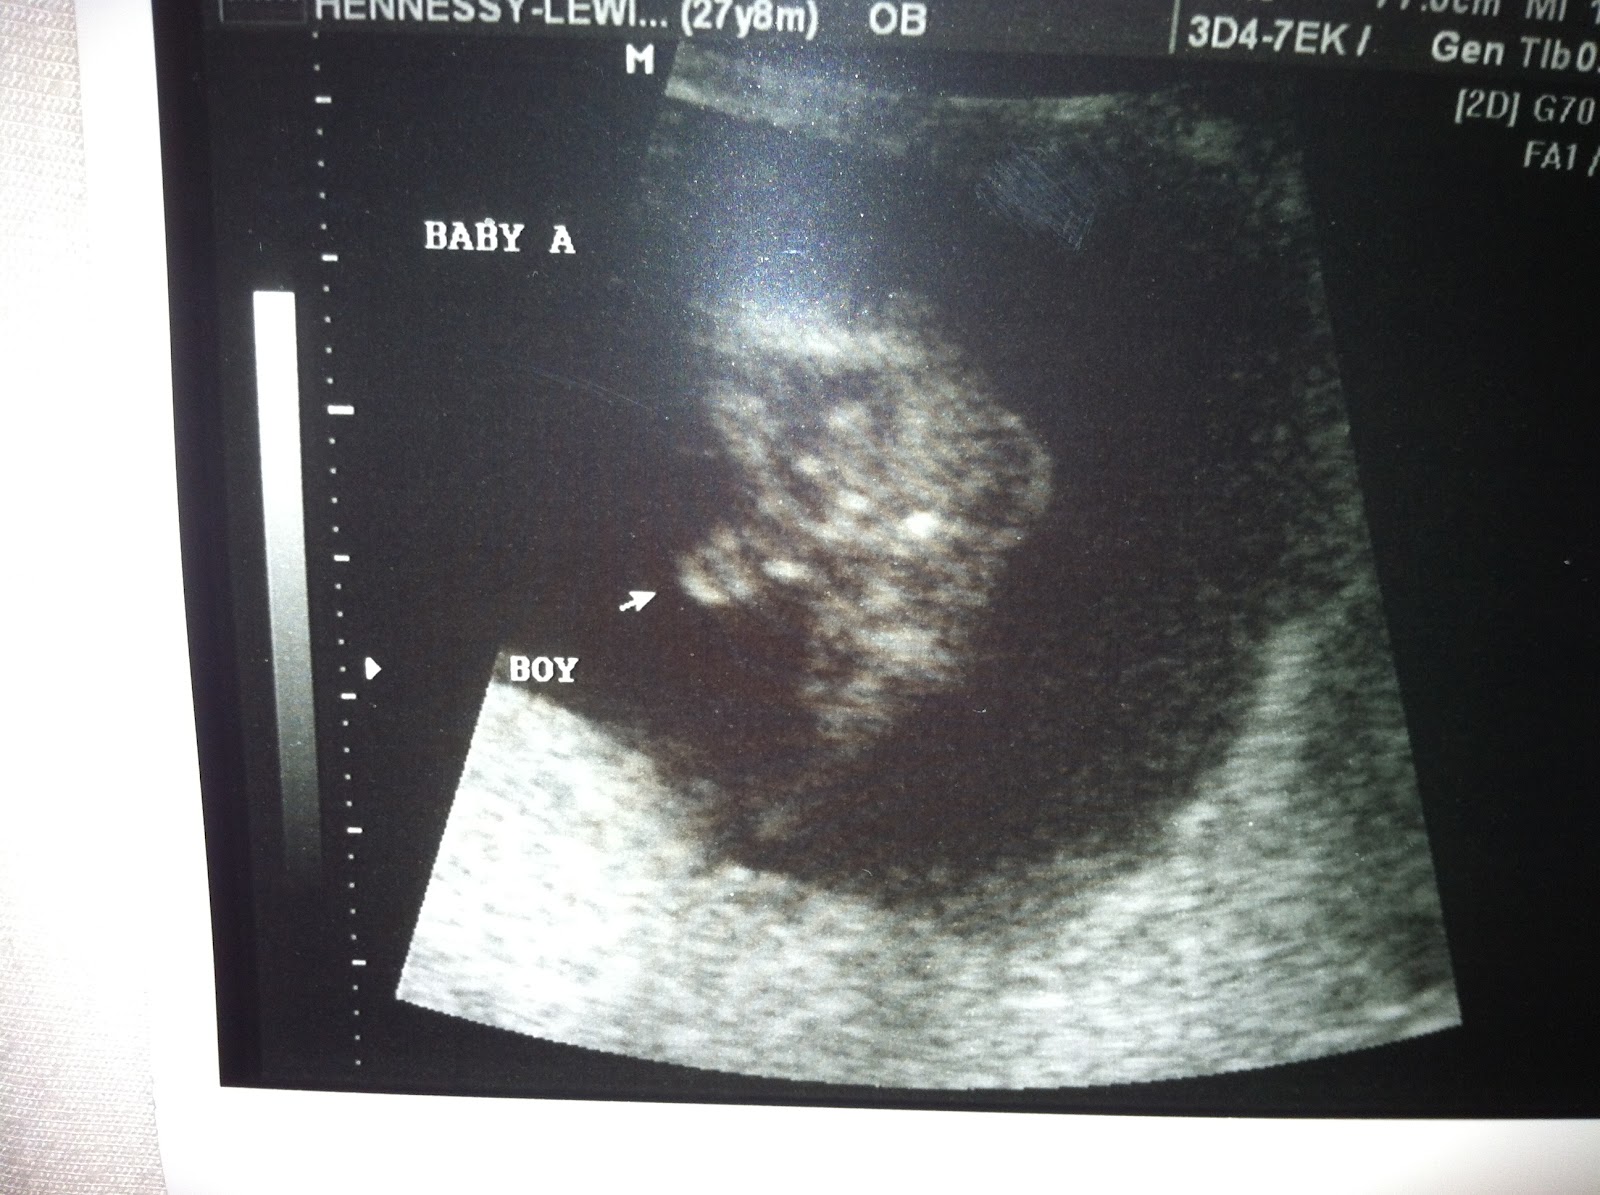

We got some big news this week... WE ARE TEAM BLUE! This was my prediction - can't mess with mother's intuition. We are so thrilled! Louie's first comment was that he was getting his own baseball team. He's going to be a great coach and more important, a great DAD! Wow, I can't believe God is going to let me have two mamma's boys. What a blessing!

That's one proud baby boy!